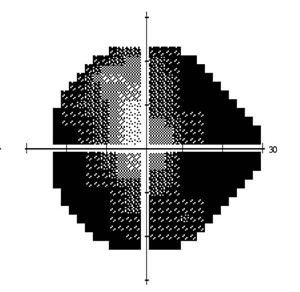

头痛、虹视、视野缺损,青光眼正在夺走你的视力

由于近视眼的眼轴拉长后,视网膜被拉扯导致视神经纤维层变薄,承受眼压的能力下降,虽然眼压正常,但已对此层脆弱的细胞造成伤害而导致视野缺损。

由于近视眼球被拉长,房角组织被拉开,高度近视患者所患的多数属于开角型青光眼,早期症状可能并不明显,但随着病情发展可出现周边视野缩小,轻度眼胀及头痛,以及一些不明确的视觉症状,如看电灯周围有彩虹圈或暗适应能力变差。后,周边视野不断缩小形成管状视野,患者注视正前方时,周围物体均看不见。

(图左:正常人的视野;图右:晚期青光眼患者的视野)